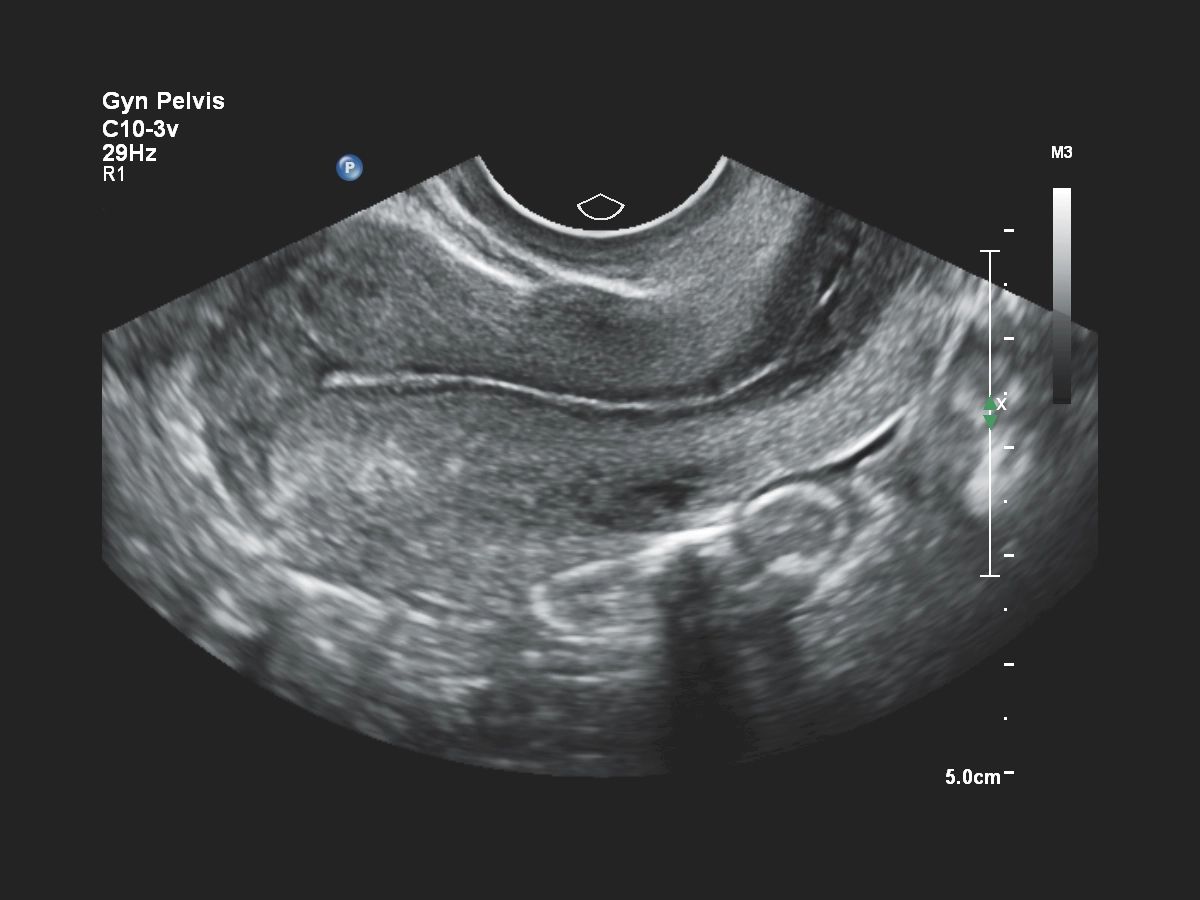

- Акушерство

- Гинекология и фертильность

Функции для гинекологии и акушерства

- Free Hand 3D - возможность реконструкции 3D изображения при помощи линейного или конвексного датчика

- 4D Imaging - автоматическая визуализация 3D/4D изображения

- Внутриполостной – Philips С10-3v PureWave